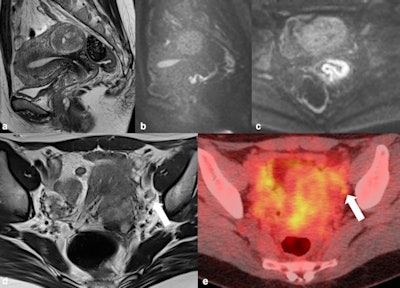

43-year-old woman. The tumor crawls on the surface of the anterior lip of the cervix to anterior fornix of vagina. (b) Sagittal and (c) axial diffusion-weighted imaging (DWI) clearly show tumor extension to the anterior vaginal fornix. Vaginal wall invasion was suspected at anterior fornix by irregularity. This case was diagnosed as stage IIA in 2017 under the previous International Federation of Gynecology and Obstetrics (FIGO) stage system. (d) Round lymph node about 8 mm in diameter was observed at the left obturator node (arrow). (e) FDG-PET/CT showed mild uptake, with suspected lymph node metastasis. At operation, lymph node metastasis was confirmed. Therefore, this case is stage IIIC1 at the present FIGO stage. Figure courtesy of BJR.